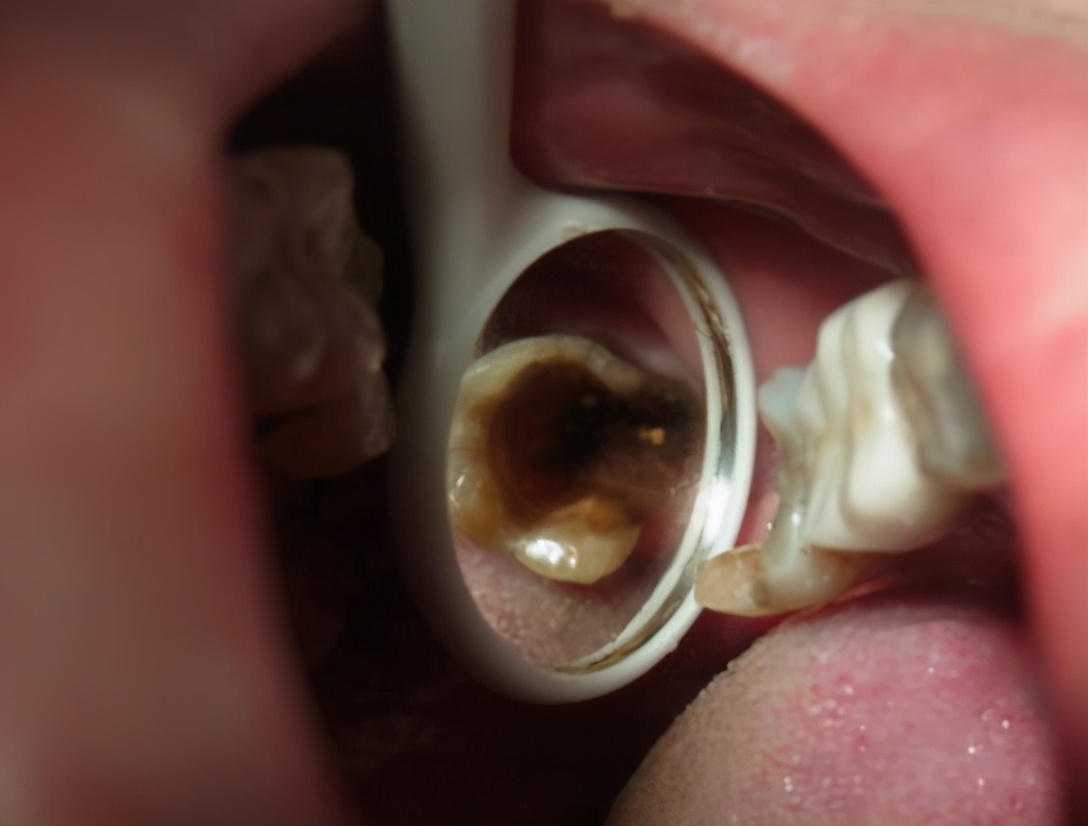

需要对牙齿情况进行详细的检查,把口腔内的不良修复体、没有保留价值的残根、蛀牙拔掉;另外有牙周病的患者也要先进行治疗控制,这样才能保证种植牙的成功率。